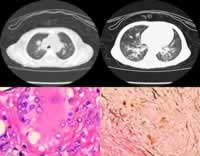

该病的致病因为神经鞘磷脂酶缺少,缺少该酶使得患者全身神经鞘磷脂代谢紊乱,神经鞘磷脂酶沉积在单核-巨噬细胞和神经组织细胞中。出现肝、脾肿大,中枢神经系统退行性变。正常肝脏中此酶的活力最高,肝、肾、脑小肠亦富于此种酶。此病患者的肝、脾等组织中该酶的活力降低至正常的50%以下。